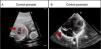

Paciente de 15 meses con diagnóstico prenatal de dilatación de la orejuela derecha desde las 20SEG, con 1,6cm2 de área en plano de 4 cámaras en la semana 35. Permaneció ingresada durante 24h tras parto eutócico a las 40,1SEG para control y monitorización cardiaca, sin presentar arritmias ni otras incidencias. Durante el seguimiento el tamaño se ha mantenido constante, observándose en el plano de 4 cámaras un área de la orejuela de 3,5cm2. Tampoco se han objetivado trombos en su interior (fig. 2). En este caso, ante la ausencia de clínica y complicaciones, se sigue actitud expectante sin iniciarse tratamiento.

Caso 2. Dilatación de orejuela derecha. A) Ecocardiografía fetal a las 22 semanas de gestación, se señala la dilatación de orejuela derecha. B) Control ecocardiográfico postnatal al año de vida con dilatación de orejuela derecha de 6mm de diámetro (flecha).AD: aurícula derecha; AI: aurícula izquierda; VD: ventrículo derecho; VI: ventrículo izquierdo.